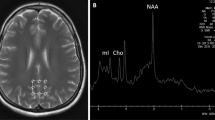

Thyroid hormones are essential factor for brain development processes, such as neuronal differentiation, growth of neurospongium, synaptogenesis and dendritic proliferation6, 7. The parasecretion of circulating thyroid hormones in hyperthyroidism influences neural function in the regions of the brain with the highest concentrations of receptors8. The changes in cerebral structure and brain function induced by hyperthyroidism are currently being researched. One study using voxel-based morphometry (VBM) reported that the gray matter volume (GMV) in the bilateral hippocampus, parahippocampal gyrus and left temporal pole was decreased in hyperthyroid patients compared to controls, but the bilateral supplementary motor area was increased9. Moreover, in a group of 28 healthy volunteers with hyperthyroidism induced by taking 250 μg of tetraiodothyronine (T4) for 8 weeks, the GMV was increased in the right posterior cerebellum but was decreased in the bilateral visual cortex and anterior cerebellum compared to euthyroid patients10. A fluorodeoxyglucose (FDG) PET study reported that hyperthyroid patients exhibited lower activity in the limbic system, frontal lobes and temporal lobes relative to healthy controls. However, compared with the hyperthyroid status, anti-thyroid therapy (treatment with methimazole, mean 77 days) induced increased metabolism in the left parahippocampal, fusiform and right superior frontal gyrus11. There was a significantly decreased glutamate concentration in the posterior cingulate cortex of hyperthyroid patients relative to controls according to in vivo proton magnetic-resonance spectroscopy (1H-MRS)12. Resting-state functional magnetic resonance imaging (fMRI) analysis revealed that hyperthyroid patients showed weaker functional connectivity(FC) from the bilateral hippocampus to both the bilateral anterior cingulate cortex (ACC) and bilateral posterior cingulate cortex (PCC) than the controls, as well as decreased FC between the right hippocampus and right medial orbitofrontal cortex (mOFC)13. In 29 subjects with hyperthyroidism induced by 8 weeks of daily oral administration of 250 μg of levothyroxine, increased connectivity between the temporal lobe and cognitive control network was observed14. Li15 regarded abnormal degree centrality(DC) in the posterior lobe of the cerebellum (PLC) and medial frontal gyrus (MeFG) as seed regions to explore the aberrant FC of patients with hyperthyroidism. They reported that abnormal FC was related to several brain functional networks, such as the default mode network (DMN), attention network and cognitive network. Based on the abovementioned studies, we speculated that changes in brain function might underlie emotional and cognitive impairments in hyperthyroid patients. However, the correlation between anti-thyroid treatment and changes in brain function remains unclear.

ALFF analysis

Before treatment, the 27 patients showed a statistically significant ALFF decrease in the right PCC compared to the 30 healthy controls (p < 0.001, AlphaSim-corrected) (Table 2, Fig. 1). However, there was no significant ALFF difference after anti-thyroid treatment. The results are summarized in Table 2 (Fig. 1).

Before anti-thyroid therapy, hyperthyroid patients exhibited lower ALFF values in the right PCC and attenuated regional FC in the bilateral PCC. These results might indicate that the PCC has a vital role in brain regions consisting of DMN to regulate cognitive and mental functions in hyperthyroid patients. Based on the highest concentration of triiodothyronine (T3) receptors, excessive thyroid hormones could induce lower glucose metabolism in the PCC with increased disease severity8. The latent mechanism might be due to elevated THs that would disrupt the basal metabolism and change the respiratory rate in mitochondria to modulate reactive oxygen species (ROS) production. Additionally, THs regulate the neuronal antioxidant mechanisms in diverse pathways5. The imbalance in oxidative stress would cause considerably more damage in nerve corpuscles than in other tissues20. Previous studies also reported that patients with hyperthyroidism showed decreased glucose metabolism in the limbic system8, 11 and significantly decreased glutamate concentrations in the posterior cingulate cortex relative to healthy controls12. Aforementioned mechanism might account for the lower ALFF values of the right PCC in our study. The PCC is considered a cortical hub in the modulation of multimodal information21. Reduced metabolism in the PCC has been identified as an early sign of Alzheimer’s disease before a clinical diagnosis21, 22. The abnormal FC of DMN was involved in cognitive impairment23, 24 and emotional disorders25, 26. Previous investigations of untreated hyperthyroidism have revealed brain regions with disrupted FC anchored in DMN13, 15. Additionally, the decreased ALFF in the right PCC was negatively correlated with the reaction time on the ANT executive network. These results imply that the PCC plays a central role in the DMN to modulate the deterioration of neuropsychological performance in hyperthyroidism.